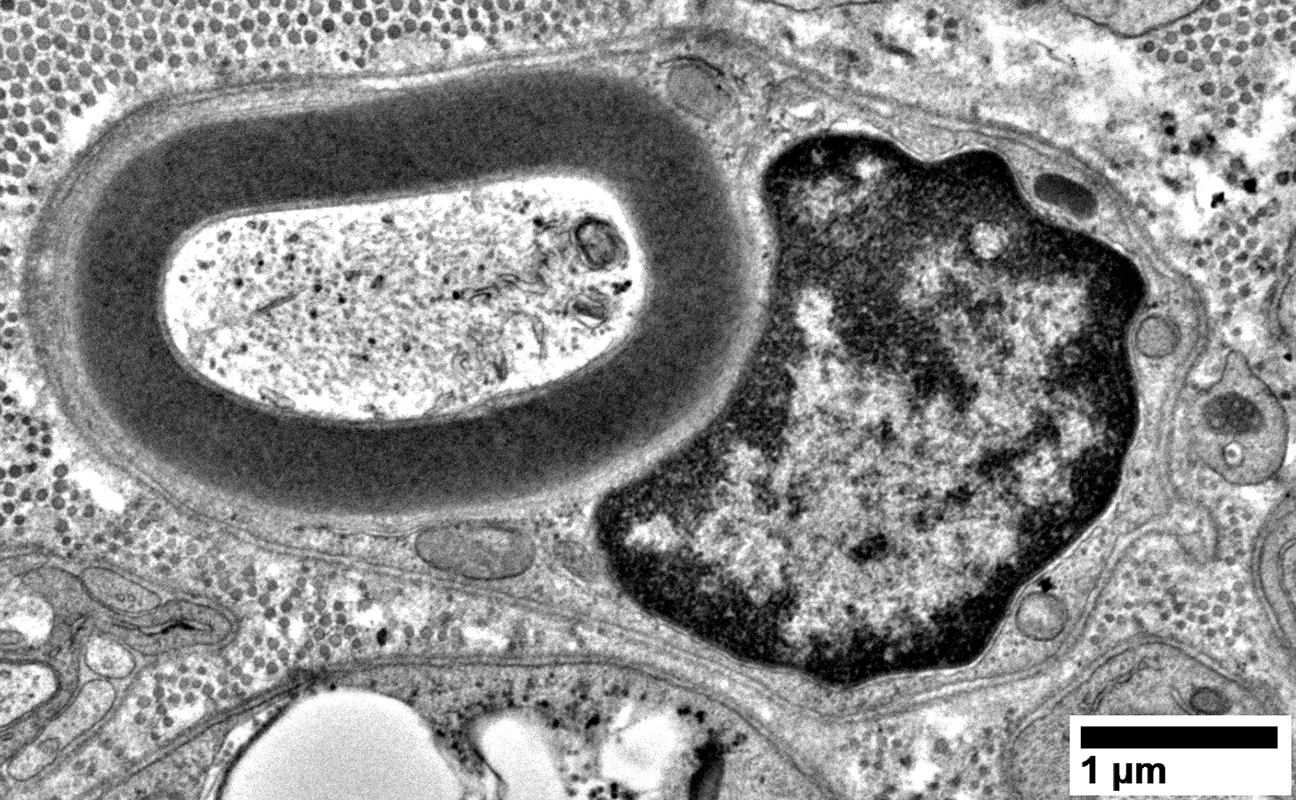

Schwann cells around Axons: Contain Myelin Degradation Products

From: R Schmidt